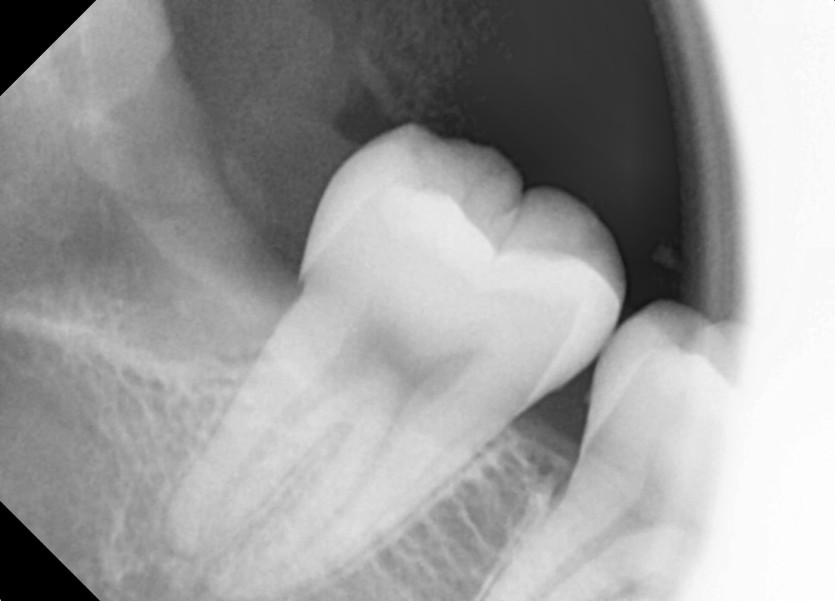

#38,48 사랑니 발치

구강 외과 전문의가 당일 발치했습니다.